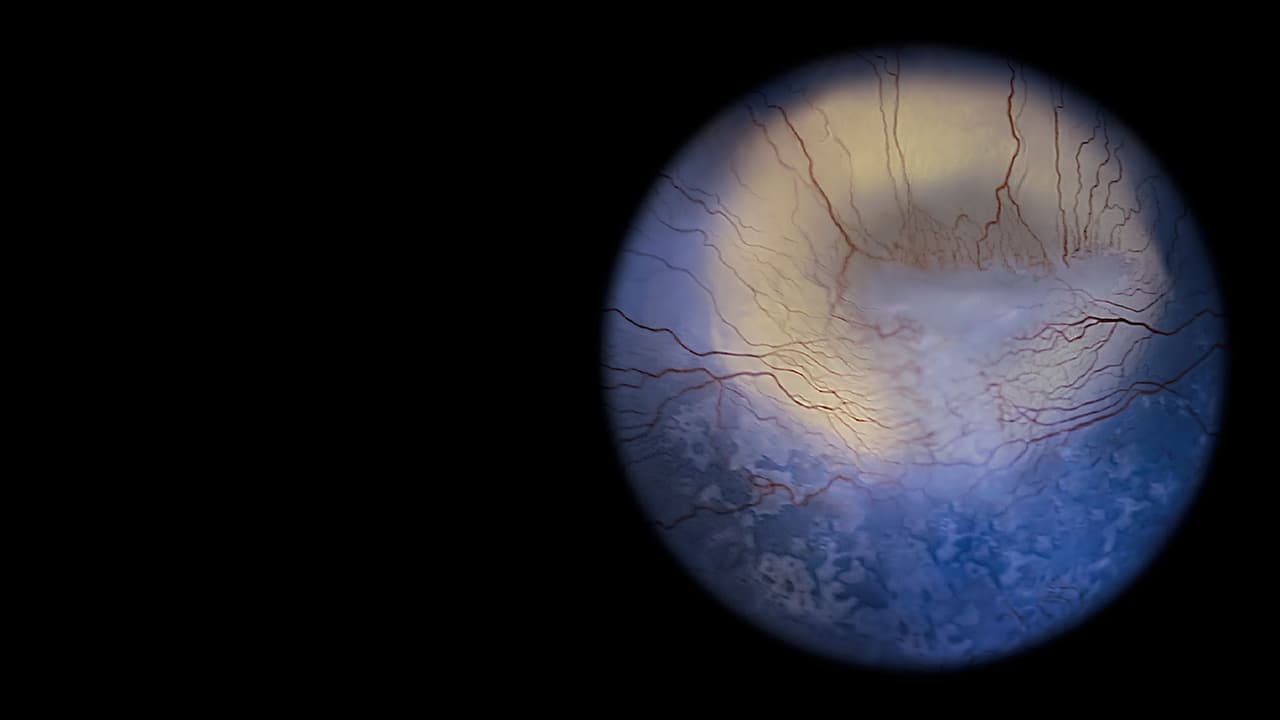

Twenty partially or totally blind people from a Naples non-profit offer an eye-opening exploration into an alternate perception of the world.